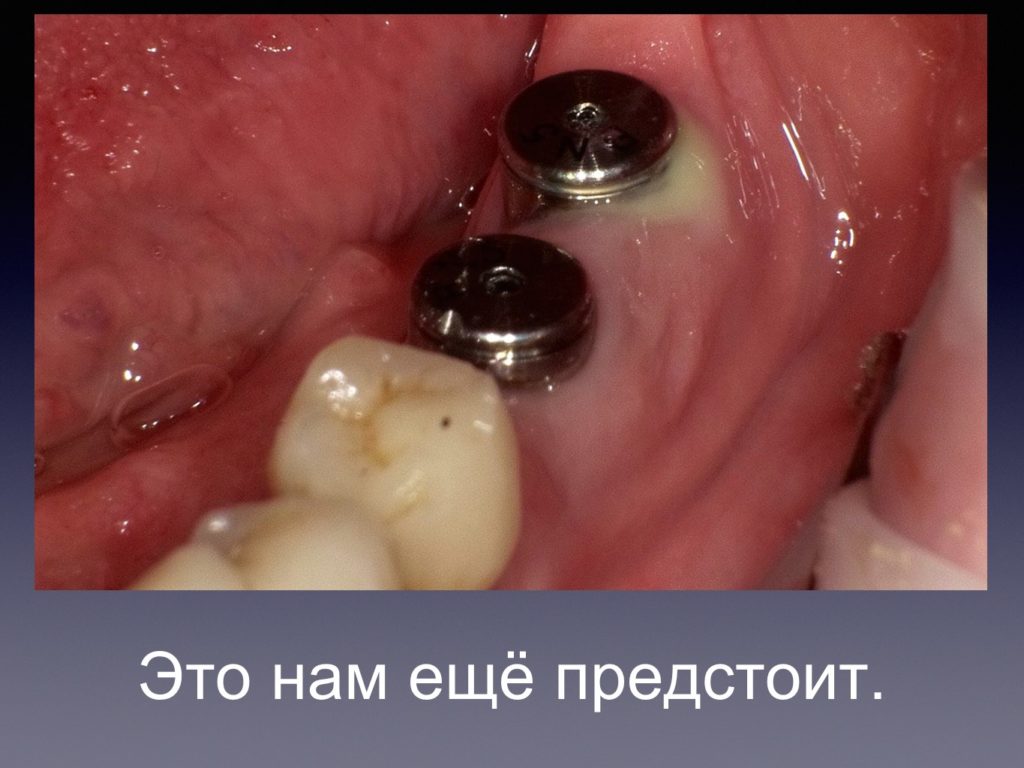

Периимплантит и БИОИМПЛАНТ ГАП -ОБНОВЛЕНО